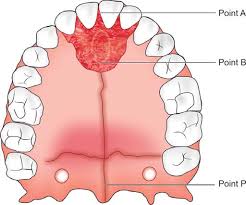

3. A szájpadba helyezett miniimplantátumok (szintén a gyökereken kívül)

Nagy sikerrel alkalmazott, biztos, kiváló csontminőségű behelyezési terület a szájpad. A szájpad középvonalába, vagy enyhén mellé helyezzük be a minicsavarokat, amikkel a felső fogív hátra/előrevitele, és felfelé mozgatása is sikerrel végezhető. Nem kell tehát félni a miniimplantátumoktól, minden esetben nagymértékben segíthetnek minket a tökéletes végeredmény elérésében. Sikerességi rátájuk 95% körül mozog! Akkor is ismertetem használatukat, ha nem biztos, hogy szükség lesz rájuk, hiszen biztosra megyünk és tökéletes mosolyt és harapást szeretnénk.